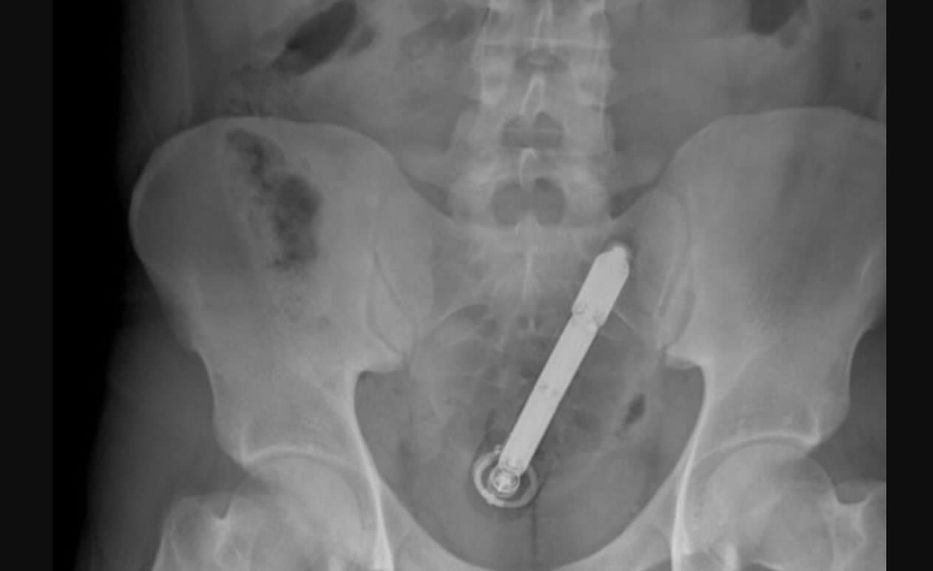

La Policía de República Dominicana investiga el caso de un hombre que llegó el pasado lunes a un centro de salud presentando un cuadro clínico poco común: tenía un objeto metálico de considerables dimensiones dentro del recto.

El hecho ocurrió el pasado lunes en la localidad de Santa Cruz de Mao, en el norte del país. Según informara el medio local El Pregonero, el individuo arribó al centro de salud “envuelto en una sábana y en condiciones delicadas”. Tras atenderlo, los médicos determinaron que la situación requería una atención que excedía la capacidad del sanatorio, por lo que lo derivaron a un hospital más grande, en la ciudad de Santiago de los Caballeros.

Versiones extraoficiales indican que el hombre habría resultado herido en un accidente ocurrido en la zona de Las Matas de Santa Cruz, mientras que otras hipótesis apuntan a un posible acto de violencia relacionado con presuntas deudas contraídas por el hombre en un expendio de drogas.

Asimismo, se dice que el sujeto podría haberse introducido el objeto por su propia voluntad, y que luego no logró retirarlo. De momento, las autoridades mantienen el hermetismo y no confirman ni desmienten ninguna de las posibilidades.

El informe menciona declaraciones de testigos que coinciden en que el sujeto, identificado como R. M. B., presentaba algunos magullones. Estas heridas no parecían consistentes con un accidente de tránsito, y abonarían la hipótesis de la agresión.